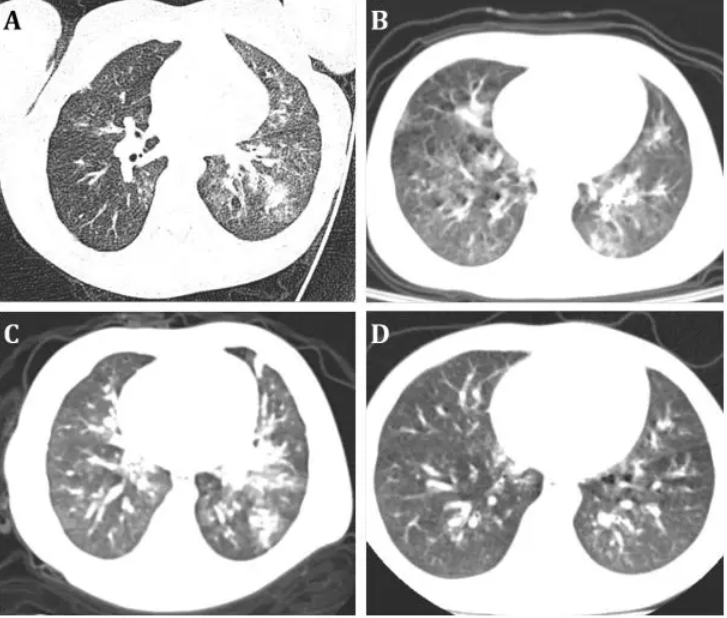

经影像学评估,6名患儿中有4名患有肺炎,胸部CT扫描显示典型的病毒性肺炎类型。